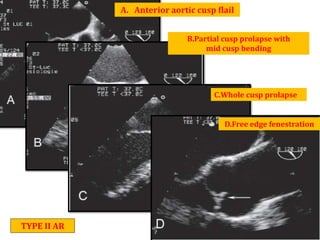

A. Anterior aortic cusp flail

B.Partial cusp prolapse with

mid cusp bending

C.Whole cusp prolapse

D.Free edge fenestration

TYPE II AR

A. Anterior aorticcusp flail B.Partial cusp prolapse with mid cusp bending C.Whole cusp prolapse D.Free edge fenestration TYPE II AR